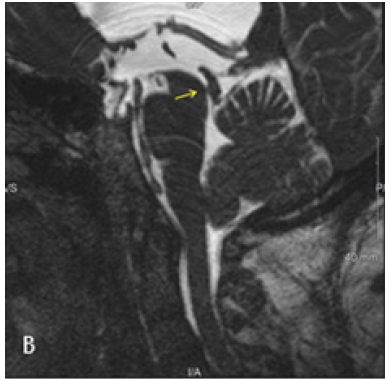

CT Brain was performed using a 128 slice Siemens Somtam Definition Edge scanner. Axial images were obtained with 5mm and 1mm slice thickness. Using the 3D MPR function on McKesson Radiology PACS station, reconstructions were performed. The sagittal reconstruction images demonstrated obstructive hydrocephalus with AW/D (Figure 1B).

Figure 1A: Axial 1mm CT slices acquired on Siemens Somatom Definition Edge scanner. Dilated bilateral lateral ventricles.

Figure 1B: Sagittal reconstruction from Axial 1 mm CT slices. Dilated lateral and third ventricles with normal appearing fourth ventricle. Yellow arrow points to the AW/D, best seen in this image 1B.

Figure 1C: Coronal reconstruction from Axial 1mm CT slices. Dilated lateral and third ventricles with normal appearing fourth ventricle. Yellow arrow points to the AW/D.